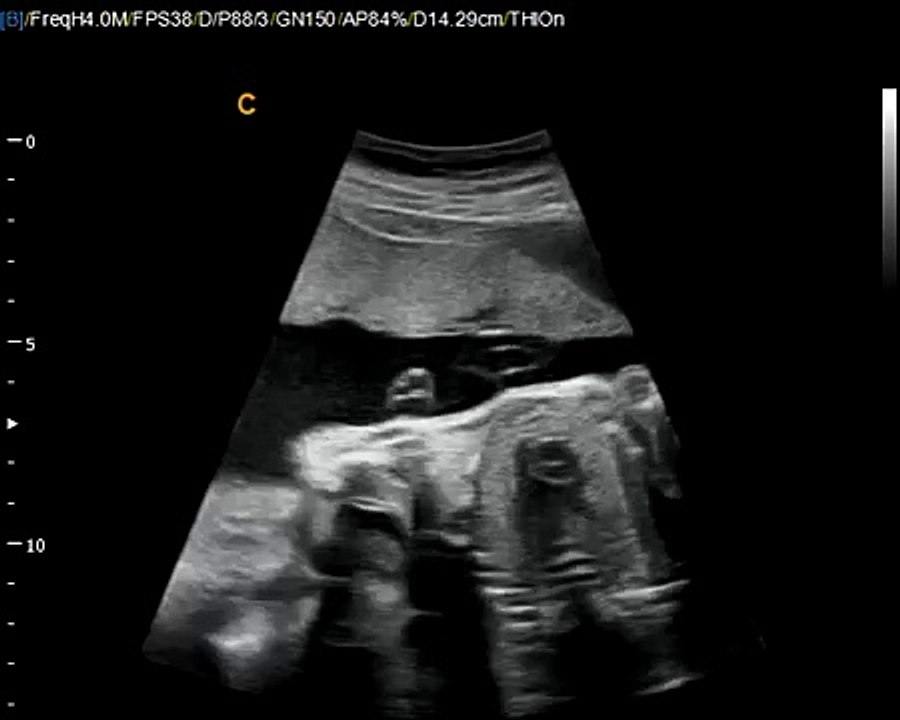

:: RO ::<br /><br />Extrase din DVD-ul 'Martor ocular - Generaţia următoare' de dr. Shari Richards.<br /><br />"O imagine valorează cât o mie de cuvinte"... mai ales dacă imaginea este realizată cu ajutorul unei tehnologii de ultimă oră! Urmarea unui alt documentar celebru - "Fereastra spre interior" ("Window to the Womb") – "Martor ocular" prezintă o călătorie fascinantă de-a<br />lungul celor 38 de săptămâni de sarcină, călătorie facilitată de tehnologia ultrasunetelor, a ecografiei 3D si 4D. Perfect pentru seminarii în scoli, pentru săli de asteptare în spitale si pentru centre de consiliere.<br /><br />Aceasta variantă are 15' şi este descriptivă (cu subtitluri).<br /><br />15' excerpt from Dr. Shari Richard's DVD 'Eyewitness - The next generation' - a fascinating journey through the womb with the newest digital ultrasound technology.<br /><br />"A picture is worth a thousand words," especially if it is from the next generation of 3D and 4D ultrasound imaging. Many of you have experienced the powerful educational and life saving effects of Shari Richard's original "Window to the Womb." Now she will take you on a fascinating new journey using the newest digital ultraound technology.<br /><br />This short version shows fetal development described using subtitles.